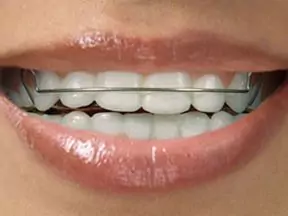

Invisalign

All of these systems, including Invisalign, use a series of clear, removable, and comfortable aligners to gradually straighten your teeth. Not only are the aligners invisible, they are removable, so you can eat and drink what you want while in treatment, plus brushing and flossing are less of a hassle. The Clear Aligner systems are not for everyone, Dr.Sonali Deshmukh will tell you if you are a good candidate for this treatment modality.